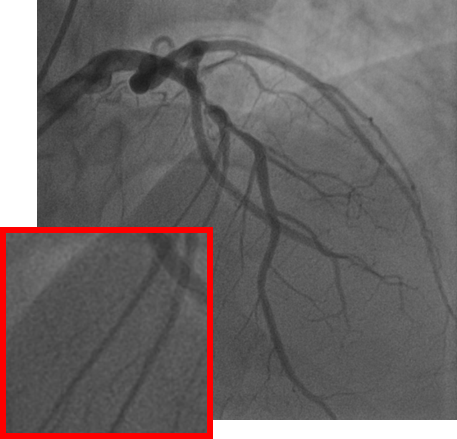

4.1 XACV Dataset

We collect 111 complete records of coronary artery X-ray videos from 59 patients, encompassing the injection, flow through the blood vessels around the heart, and dissipation of the contrast agent. Subsequently, we establish the XACV (X-ray Angiography Coronary Video) dataset. Each video consists of an average of 86 frames of high-resolution coronary artery X-ray images, with an equal distribution of left and right coronary arteries. We invite experienced radiologists to annotate the vascular regions, focusing on one or two frames where the contrast agent is most prominent in each video. These annotations are used only for evaluation in our method, not for training, maintaining the unsupervised nature of our approach. The data collection protocol involves several key steps, including patient preparation with informed consent and metal object removal, image capture using a Philips Allura Xper FD20 machine for standardized frontal (PA) and lateral views, DICOM file storage, and de-identification for patient privacy. Experienced radiologists perform diagnostic annotations using standardized tools and methods, with multiple annotations to enhance accuracy. Quality control measures, secure data management, and strict adherence to ethical guidelines and privacy regulations are implemented throughout the process. The XCAD dataset contains only a single image, and the CADICA video dataset does not provide corresponding ground truth. Therefore, in the following experiments, we conduct all the analyses on our collected XACV dataset and the corresponding GT for each sequence. In Figure 5, we show that compared to other publicly available datasets, XCAD (Ma et al., 2021) and CADICA (Jiménez-Partinen et al., 2024), our dataset exhibits finer annotations in the vascular regions, providing an advantage for future related tasks. The development and use of our dataset have been approved by our institution’s IRB. We will make the XACV dataset publicly available.